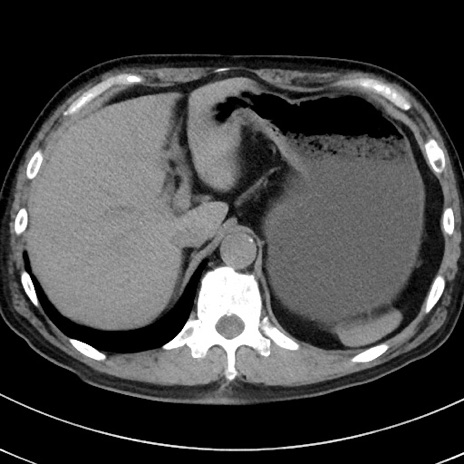

症例38(横断像)

【症例】70歳代 男性

【主訴】腹痛・嘔吐

【現病歴】昨晩より、嘔吐・腹痛あり。今朝になっても嘔吐あり。来院。

【既往歴】心臓バイパス手術、開腹胆摘、腸閉塞

【身体所見】BP 107/71mmHg、HR 116/min、腹部:平坦、軟、下腹部に軽度圧痛あり。反跳痛なし。

【データ】WBC 15100、CRP 0.32